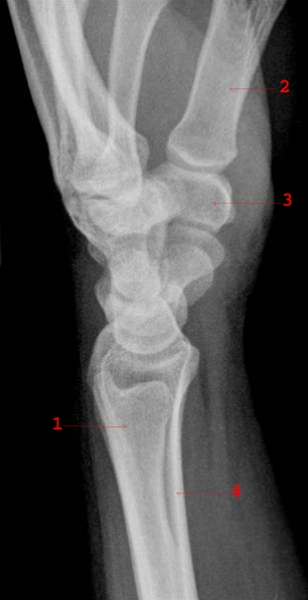

Normalt sidebillede af håndled med håndrodsknogler.

1. Ulna

2. 1. metakarp

3. Os trapezium

4. Radius